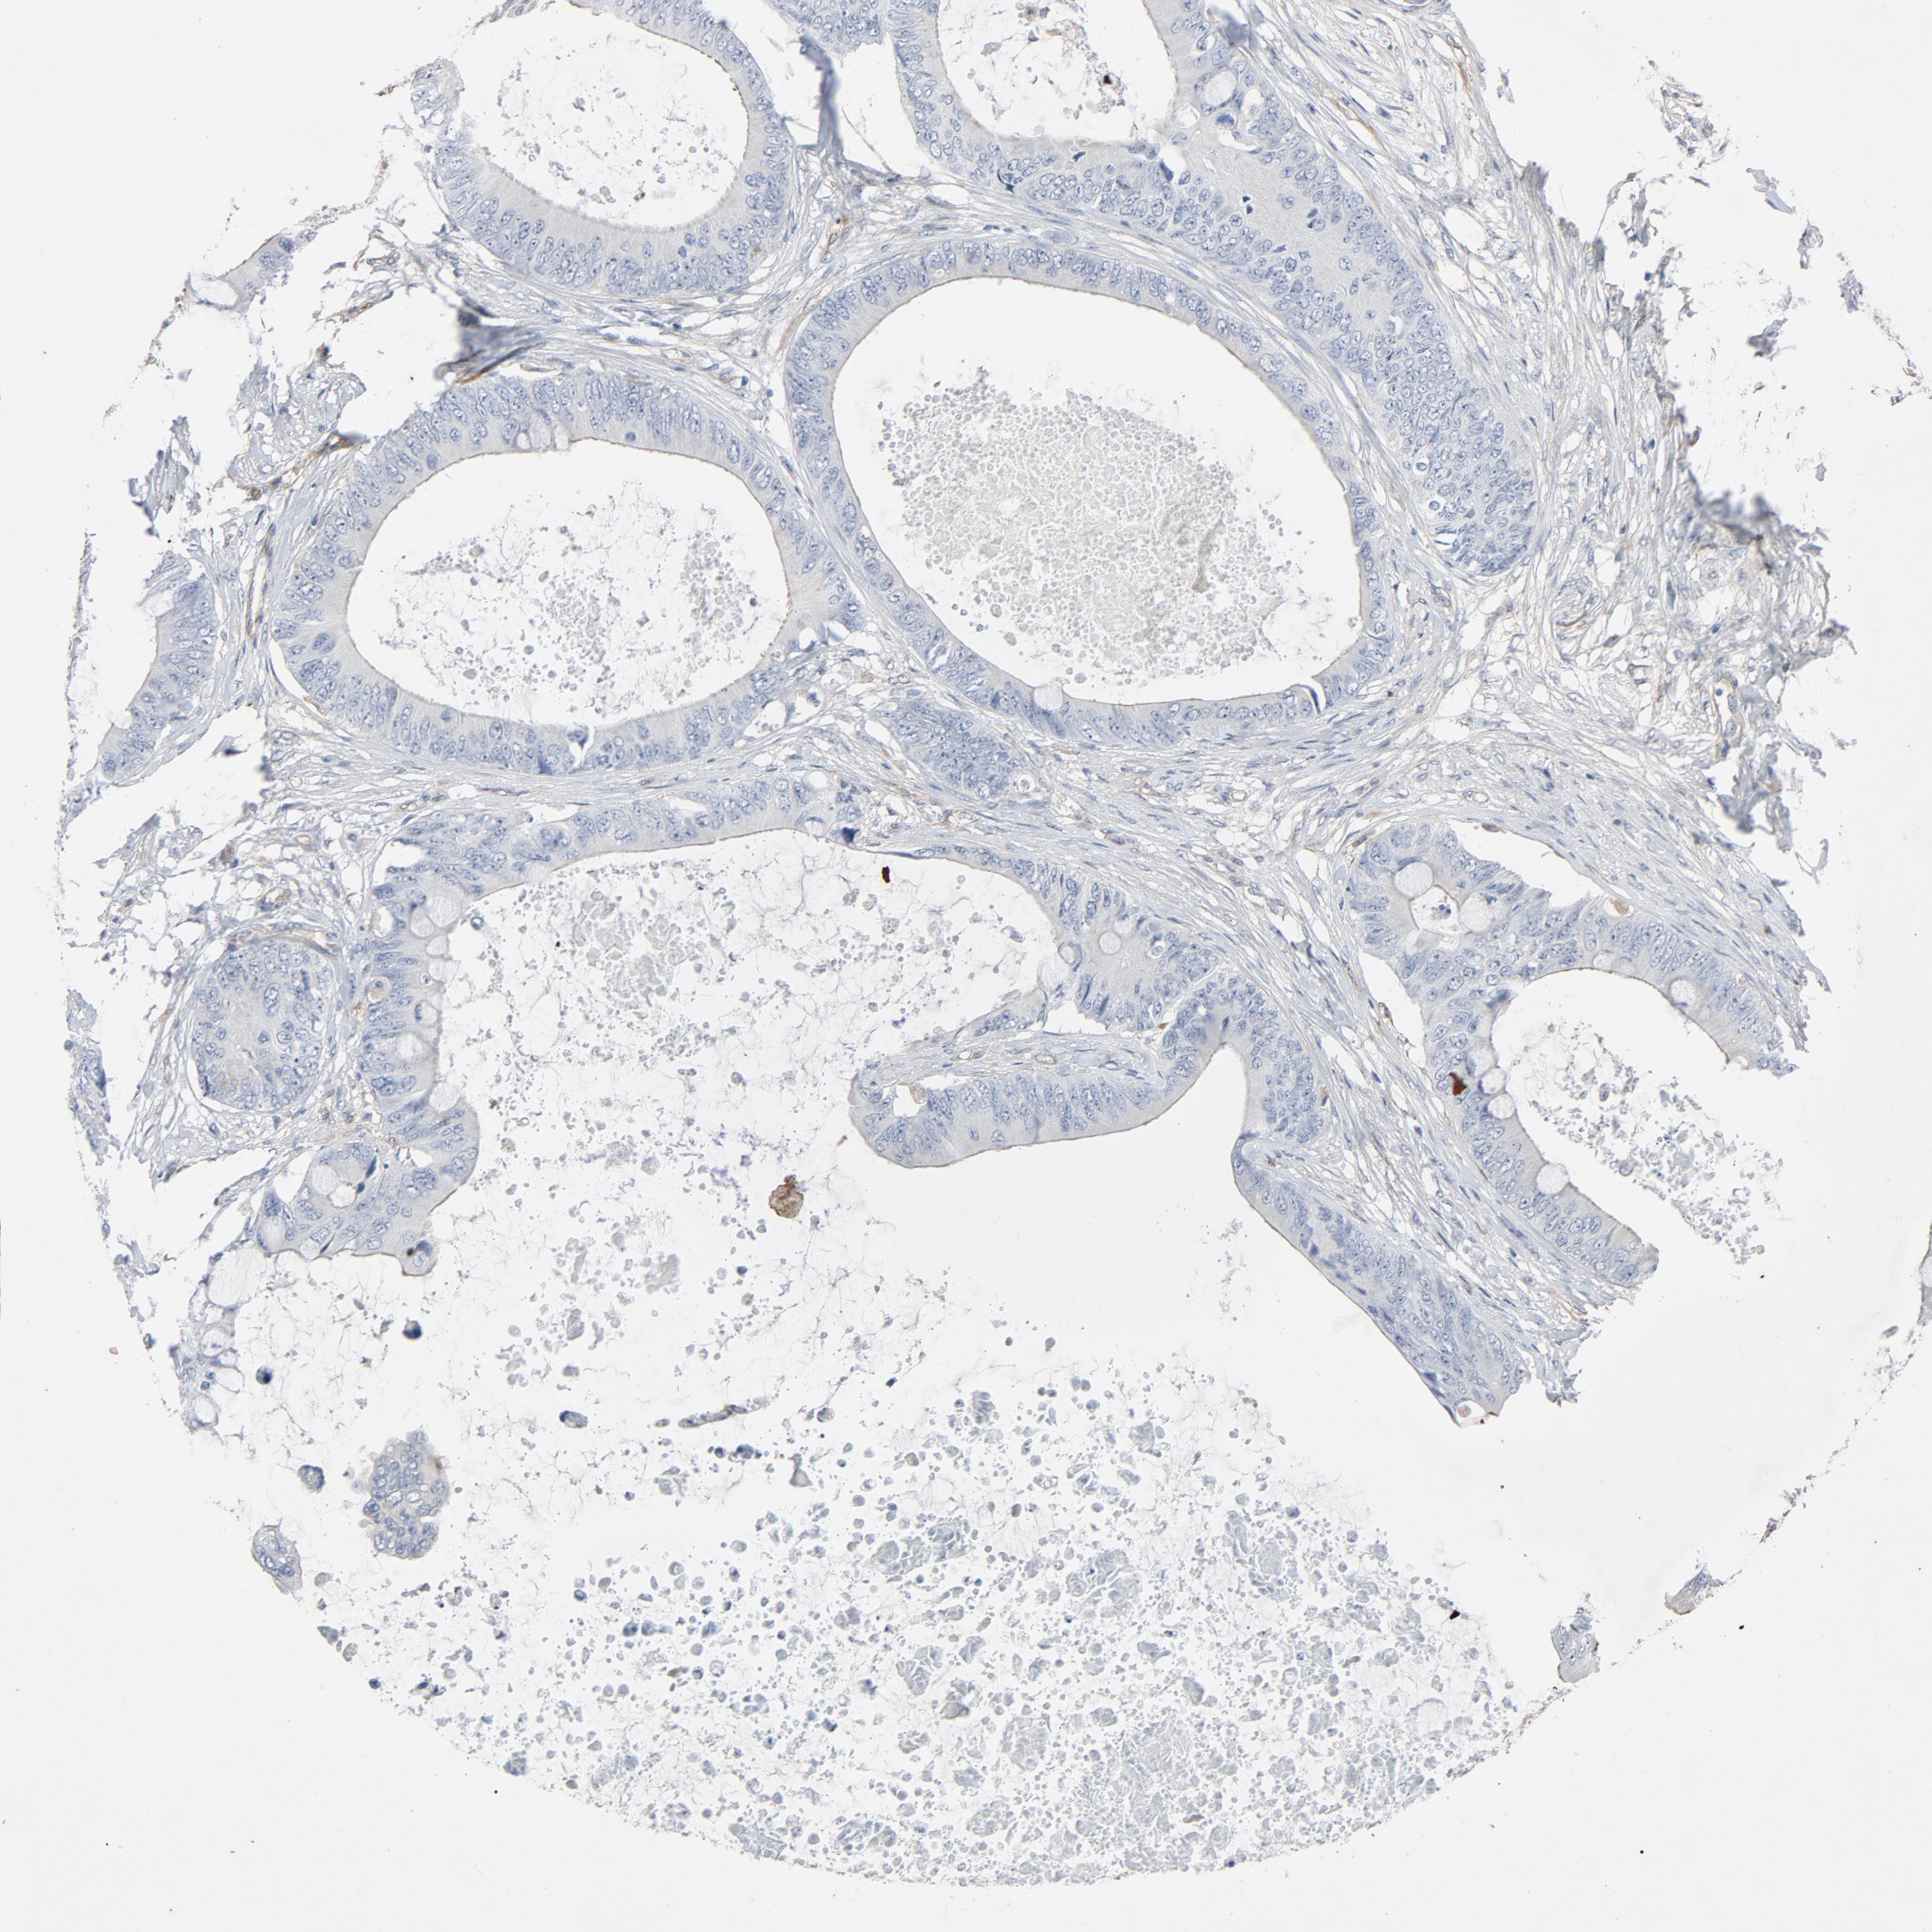

CANCER COLORECTAL CANCER Show tissue menu

Colorectal cancer

Human cancer

Colon adenocarcinoma